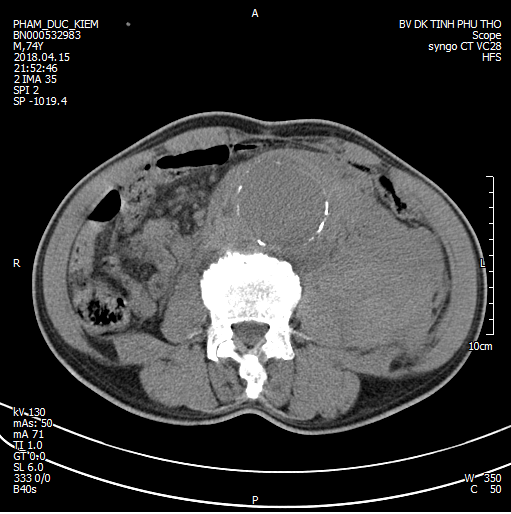

Khối phình động mạch chủ (ĐMC) và máu tụ lớn

Người bệnh đã được hồi sức tích cực, duy trì huyết động và chụp cắt lớp vi tính 128 dãy, xác định phình động mạch chủ bụng ngay dưới phân chia động mạch thận, lan tới ngã 3 động mạch chủ - chậu, vỡ vào khoang sau phúc mạc, tụ máu lớn sau phúc mạc. Siêu âm tim xác định hở van động mạch chủ nhiều.